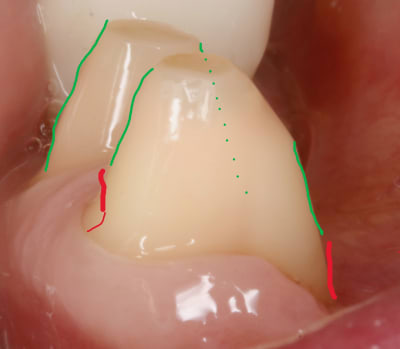

arrive maintenant le congé .

on a vu qu en vest , du fait que ce soit penché à cause des dents du haut , ce serait bien de rajouter une opposition avec la face linguale .

donc au pied si on pouvait rentrer un peu tout en redressant ce serait pas mal .

ben voilà , il sert à ca le congé , le voilà . à faire la férule de PP :-)

le congé doit donc servir à réduire la conicité .

c est pour ca qu il doit être fait APRES la face linguale .

puisque que peuchère , la face linguale étant limitée , on s adapte à elle et on parallélise à mort , enfin on essaye .

traits rouges sur photos .

bon maintenant on va s occuper des autres .

donc on les parallélise aux canines sur les faces vest .

traits verts sur photo

alors oui tu risques d avoir des trognons coniques .

et c est là que tu ressors le congé . c est en faisant les congés en vest que tu rentres le pied des dent et donc que tu réduis la conicité .

conicité , je le rappelle , par exemple , entre vest de 44 et de 34 , hein , faut pas l oublier ça . sinon c est la contre dépouille direct .

mais tu comprends aussi tres vite que plus ton congé est large plus tu perds de la rétention , puisque si tu prends une grosse fraise , en quart de rond , toute la partie arrondie va te faire une découpe horizontale qui elle ne te servira à rien quand à la rétention par contre elle te servira à bien niquer la dent .

moralité le gros congé ça ne peut pas aller .

a la limite tu peux faire un double congé en espérant rajouter un peu de partie verticale .

ici sur les canines ça nous arrange pour avoir des dents plus fines .

traits noirs sur la photo .

bref , tout ça pour dire que le style de taille n est pas du à un concept ésotérique , genre que moi je la veux pointue , que lui la préfère droite , et que ci que là .

non , on a vu sur les photos que chaque trait de couleur ( donc de découpe ) est une réponse à une fonction qui s ajoute .